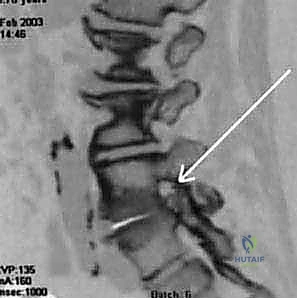

- التصوير بالرنين المغناطيسي (MRI): هو المعيار الذهبي لتشخيص تضيق القناة الشوكية. يوفر صوراً ثلاثية الأبعاد وعالية الدقة للأنسجة الرخوة، بما في ذلك الأقراص، الأربطة، والأعصاب، مما يسمح للطبيب برؤية مكان ومقدار الضغط بدقة متناهية.

- التصوير المقطعي المحوسب (CT Scan): يُستخدم لتقييم الهياكل العظمية بشكل أفضل، مثل النتوءات العظمية وسماكة العظام. غالباً ما يُستخدم للمرضى الذين لا يمكنهم الخضوع للرنين المغناطيسي.